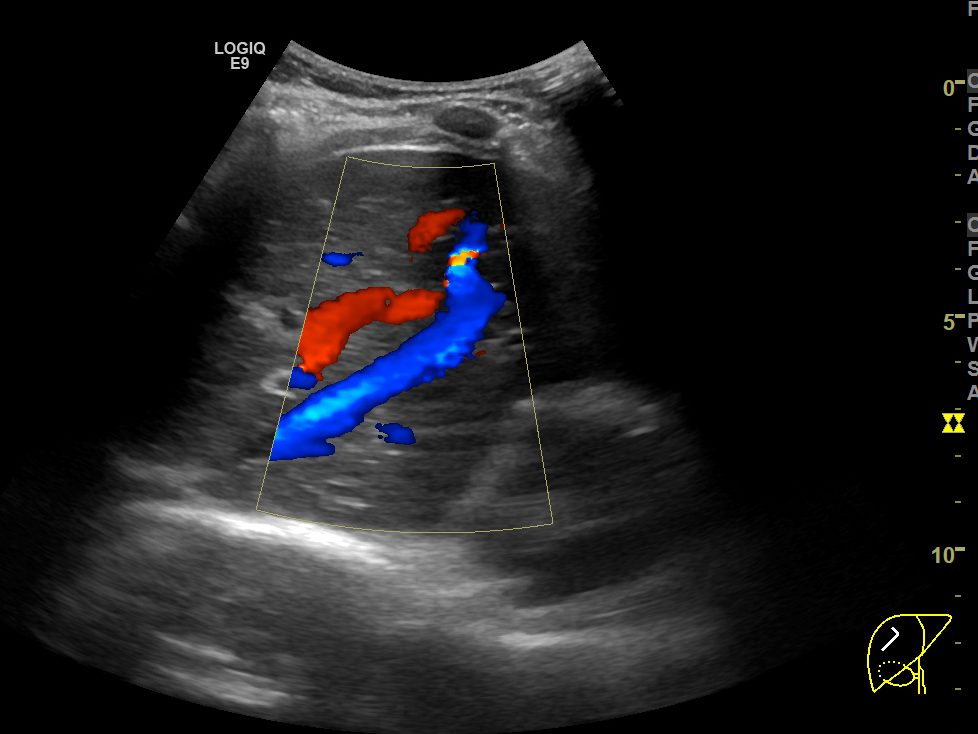

위의 두 영상은 간초음파에서 우간정맥(Rt. hepatic vein)의 장축을 따라 얻은 B모드 및 컬러도플러 영상입니다. 간실질 에코가 매우 거칠고 불균일한 만성 간질환 환자인데, 도플러영상에서 장축 전체에 걸쳐 뚜렷하게 확인할 수 있는 우간정맥이 B모드영상에서는 희미하게 일부분만 보입니다. 심지어 확인되는 부분도 컬러 도플러영상에서 보이는 것보다 훨씬 가늘어보이죠.

반면, 혈류가 반대방향이어서 빨갛게 보이는 간문맥(Rt. portal vein)의 경우는 B모드 영상에서도 간문맥 벽이 뚜렷하게 보일 뿐 아니라, 굵기도 컬러도플러 영상에서 확인되는 것과 별로 큰 차이가 나지 않습니다.

간초음파를 시행하면서 확인해야 하는 표준영상 중에는 우간정맥의 장축을 포함하는 영상이 포함되어있습니다. 마찬가지로 간좌엽의 시상면영상을 확인할 때에도 좌간정맥(Lt. hepatic vein)이 포함되어 촬영하는 게 보통입니다. 그렇게 간정맥을 확인하는 과정에서 위와 같이 간정맥이 잘 보이지도 않고, 실제 직경보다 훨씬 작게 보이는 이런 현상은 현장에서는 굉장히 흔한 현상입니다.

B모드영상에서 간정맥이 실제보다 훨씬 얇고 희미하게 보이거나, 아예 잘 보이지 않는 이유는 간정맥의 혈관벽이 얇아서 초음파신호가 반사되지 않아 영상에서 혈관벽을 특정할 수 없기 때문입니다. 특히 간실질의 에코음영이 거칠거나 간섬유화가 심하게 진행된 만성 간질환 환자들에서 간정맥을 확인하지 못하거나, 굉장히 가늘게 보이는 경우가 많습니다.

위의 영상들은 모두 GE사의 logiq E9 장비를 통해 얻은 영상입니다. 혹시 몰라 tissue harmonic image모드를 꺼놓거나, 다른 영상옵션들을 조절해봐도, 간정맥이 실제보다 가늘거나 희미하게 보이는 환자분들에서 일반적인 B모드영상보다 간정맥을 더 또렷하게 보여주는건 불가능했습니다. 지난 17년 내내 GE사의 초음파장비만을 써와서 타사 장비들의 상황을 비교해보지 못했지만, 어쨋던 GE사의 장비들 만큼이라도 이런 한계점을 극복해서 더 나은 영상을 담보할 수 있게 발전했으면 좋겠습니다.

그런 장비의 발전과 진보가 있기 전까지는 간초음파의 표준영상을 얻는 과정에서 간정맥, 특히 우간정맥의 장축을 보여주는 영상을 촬영할 때에는 좀 더 번거롭더라도, 컬러도플러영상을 함께 촬영하면서 우간정맥을 확인하는 것도 좀 더 신뢰할만한 간초음파영상을 얻기 위해 권장될 수 있겠다는 생각입니다.